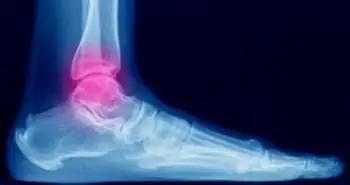

Ankle fracture-dislocation occurs more commonly in elderly diabetic females with poor functional outcomes.

As per a study published in 'Foot & ankle specialist' by Tantigate D and researchers, the ankle fracture-dislocation is more frequent in patients who were older, female, and diabetic.

Substantial injury to the bony and soft tissue structures of the ankle is known as fracture dislocation of the ankle. Only limited reporting of functional outcome of ankle fracture-dislocations have been studied so far. Hence, this retrospective chart review focused on distinguishing the functional outcome after open reduction internal fixation in ankle fractures with and without dislocation.

This review of surgically treated ankle fractures spanned over 3 years. The fracture type, demographic data, operative time and complications were noted. Thirty-three (28%) patients out of 118 patients eligible for analysis sustained a fracture-dislocation. The mean patient age was 46.6 years. Sixty-two patients, who had a follow-up of at least 12 months, were investigated for functional outcome using Foot and Ankle Outcome Score (FAOS). Median follow-up time was 37 months.

The demographic variables and FAOS were compared between ankle fractures with and without dislocation. The average age of patients sustaining a fracture-dislocation was higher (53 vs 44 years); with a greater percentage being female (72.7% vs 51.8%) and diabetic (24.2% vs 7.1%). Both groups witnessed similar wound complications. Generally, FAOS was poorer in the fracture-dislocation group; nonetheless only the pain subscale portrayed statistical significance (76 vs 92).

The researchers of this study concluded that at a median of just > 3-year follow-up, functional outcomes in fracture-dislocations were generally poorer and also, the pain subscale of FAOS was worse in a statistically significant fashion.